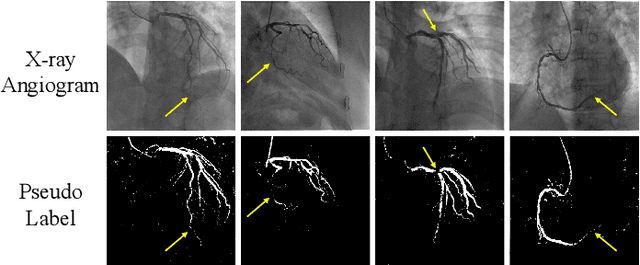

Abstract:The segmentation of coronary arteries in X-ray angiograms by convolutional neural networks (CNNs) is promising yet limited by the requirement of precisely annotating all pixels in a large number of training images, which is extremely labor-intensive especially for complex coronary trees. To alleviate the burden on the annotator, we propose a novel weakly supervised training framework that learns from noisy pseudo labels generated from automatic vessel enhancement, rather than accurate labels obtained by fully manual annotation. A typical self-paced learning scheme is used to make the training process robust against label noise while challenged by the systematic biases in pseudo labels, thus leading to the decreased performance of CNNs at test time. To solve this problem, we propose an annotation-refining self-paced learning framework (AR-SPL) to correct the potential errors using suggestive annotation. An elaborate model-vesselness uncertainty estimation is also proposed to enable the minimal annotation cost for suggestive annotation, based on not only the CNNs in training but also the geometric features of coronary arteries derived directly from raw data. Experiments show that our proposed framework achieves 1) comparable accuracy to fully supervised learning, which also significantly outperforms other weakly supervised learning frameworks; 2) largely reduced annotation cost, i.e., 75.18% of annotation time is saved, and only 3.46% of image regions are required to be annotated; and 3) an efficient intervention process, leading to superior performance with even fewer manual interactions.